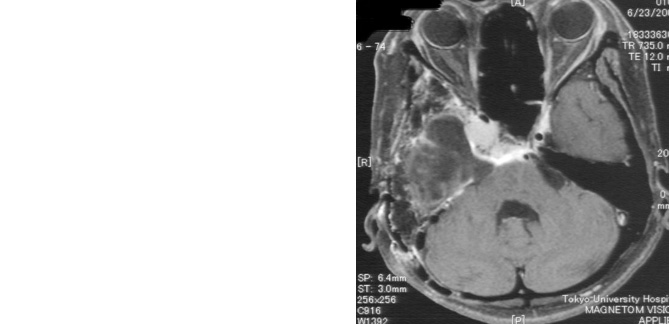

症例2は巨大斜台髄膜腫の症例です。歩行障害・嚥下困難などの症状をもち来院されましたが、腫瘍の大半を切除し、歩いて帰宅することが出来ました。海綿静脈洞部分の腫瘍は取ると合併症が出現するため、この部分は意図的に残しガンマナイフ治療を計画しています。

図2 頭蓋底髄膜腫 48歳女性 歩行障害、嚥下困難で来院

術後MRI:海綿静脈洞への浸潤部を除き

摘出、歩行障害改善し退院